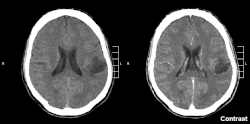

Gliom je typ tumoru, jenž vzniká v mozku nebo míše. Název gliom je odvozen z glie. Gliomy tvoří cca 30 % všech intrakraniálních tumorů a 80 % všech maligních tumorů [1] Mezi gliom se řadí astrocytom, oligodendrogliom, glioblastom, ependymom, gliom mozkového kmene, tj. dělení je nikoliv podle lokace vzniku ale podle toho, u kterých typů buněk se příznaky manifestují.